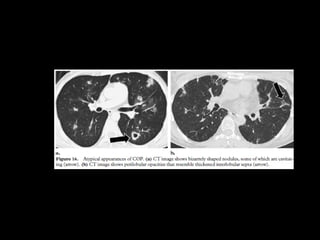

COP

• Ex BOOP

COP CT

• Consolidaciones parcheadas

• Broncograma aéreo Signo halo inverso

• Vidrio esmerilado periférico o peribroncovascular

• Crazy paving

• LI

• Nódulos, cavitarse

• Puede simular neumonía

• Reticulación subpleural

• Derrame pleural

COP CT • Consolidacionesparcheadas • Broncograma aéreo Signo halo inverso • Vidrio esmerilado periférico o peribroncovascular • Crazy paving • LI • Nódulos, cavitarse • Puede simular neumonía • Reticulación subpleural • Derrame pleural

Bilateral or unilateralpatchy alveolar airspace consolidation is revealed, often subpleural and peribronchial in location and mainly in the lower zones. Generally, the infiltrates gradually enlarge from their original size or new infiltrates appear. Consolidation is often nonsegmental and varies from 2 to 6 cm in diameter. Cavitary BOOP that mimics tuberculosis and cavitating opacity after lung transplantation has been reported. An air bronchogram may be present. Nodules 3-5 mm in diameter are seen in approximately one half of patients; nodules may be migratory. Basal linear opacities are linked to a poorer prognosis. Unilateral focal or lobar consolidation occurs in 5-31% of patients. Miliary pattern is rare. Pleural thickening occurs but pleural effusions are rare.